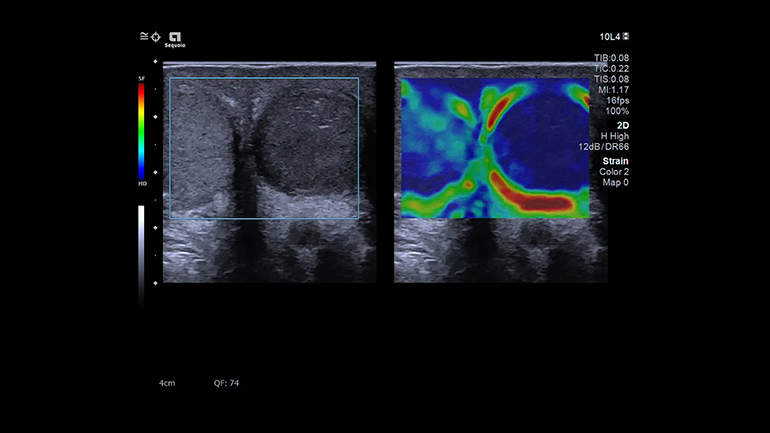

Strain. Деформация

Strain-режим визуализации отличается очень высокой чувствительностью к деформации, что позволяет использовать вместо циклов принудительного сжатия естественную компрессию, создаваемую дыханием пациента и сердечными сокращениями для получения эластограммы относительной жесткости.